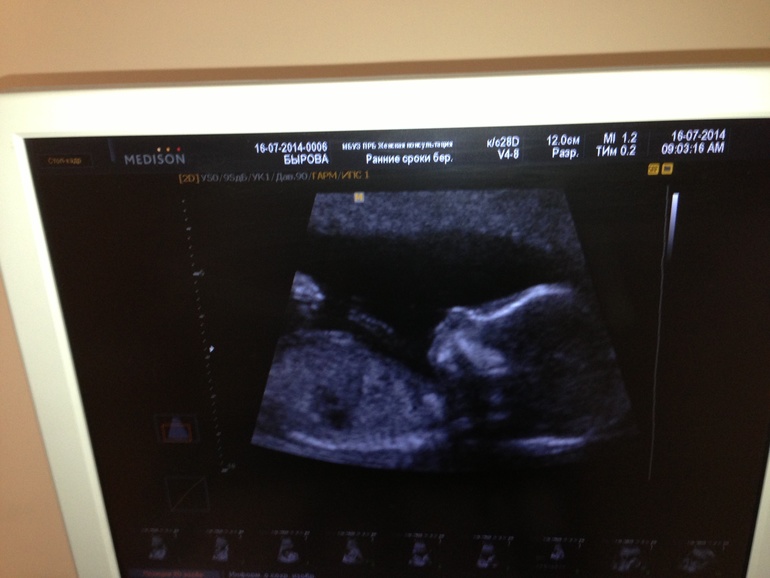

После всех этих больниц и лекарств я собираюсь завтра записаться на узи, последний раз в 19 н делала. Было все ок!